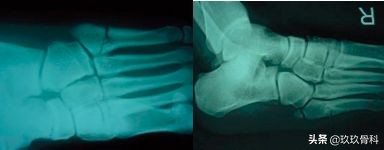

第五跖骨疲劳骨折